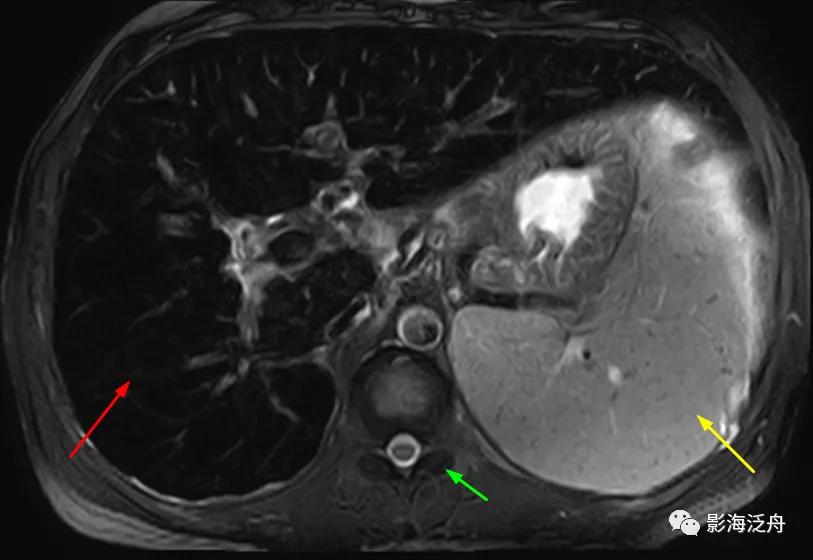

增强动脉期,患者肝实质呈弥漫性斑点状强化(类似于粟粒型肺结核),这种强化方式可能与动脉及门脉的细小分支异常分流及部分肝组织灌注不良有关。门脉期及静脉期患者肝实质呈较均匀强化(未给出图像),提示病程相对可逆。

与正常人对比可以更好地观察上述图像特征,注意肝损伤患者的肝脏强化程度整体较低(以脾脏强化程度作为参照,两幅图像的强化时间大致相仿),但平衡期强化程度并无异常减低(未给出图像)。